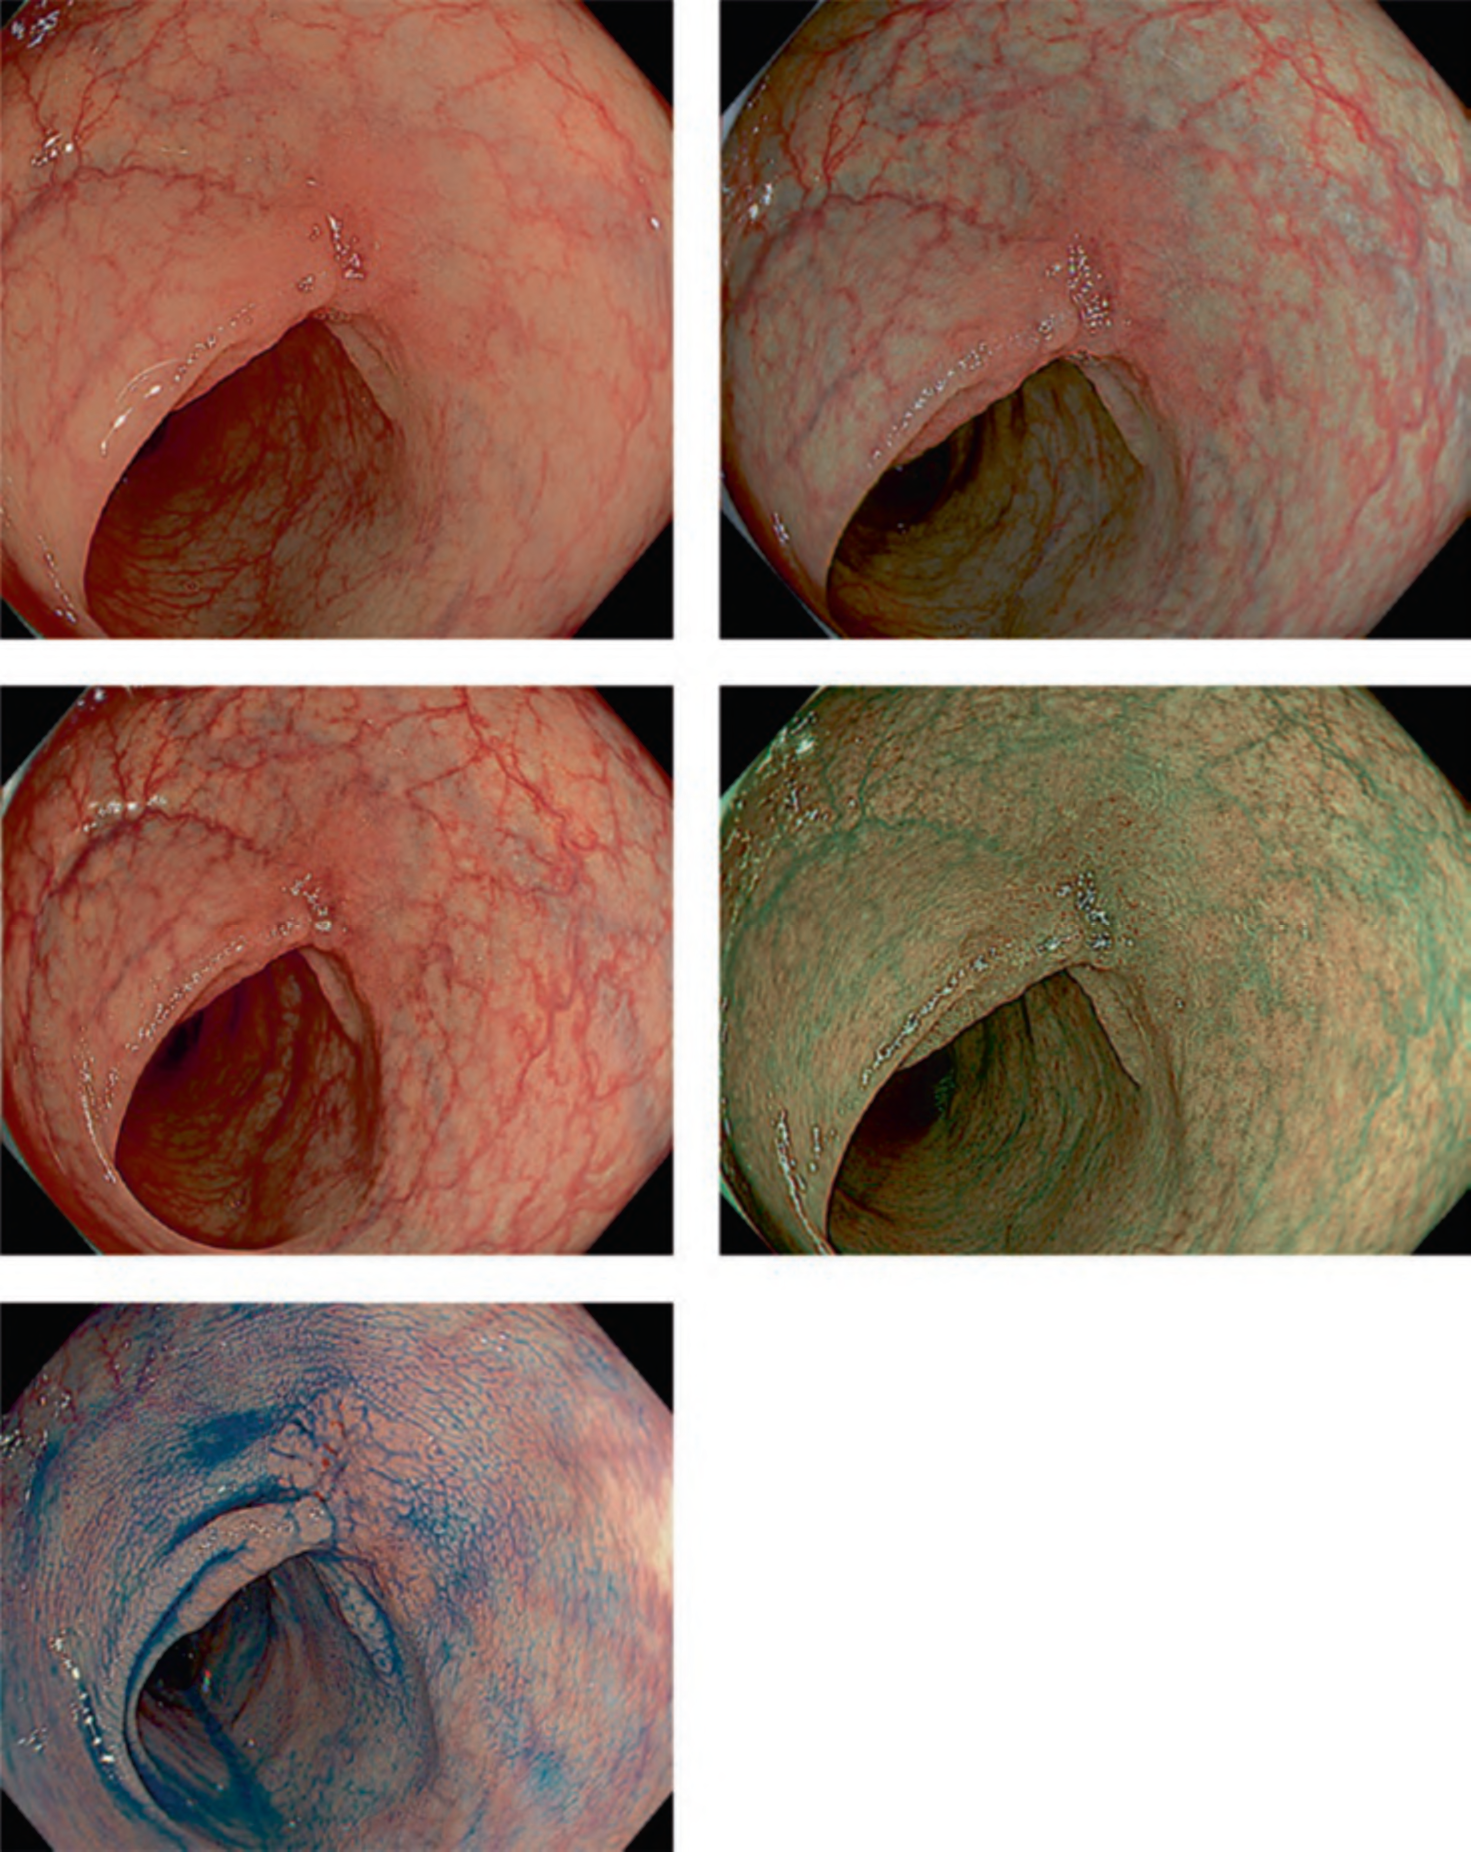

Figure 2 illustrates the features of the TXI. In TXI modes 1 and 2, gaps between the nodules were more distinctly depicted than in WLI and narrowband imaging (NBI). Furthermore, owing to the emphasis on brightness of the distal portion, the appendix orifice can be more clearly observed with TXI than with WLI. In TXI mode 1, pale areas appear even paler, and red areas appear redder, indicating a stronger contrast in color tone compared with white light. Conversely, in TXI mode 2, color tones are not emphasized, allowing for observation more similar to WLI conditions. Both TXI modes 1 and 2 offer improved visualization of vessels in the mucosa, particularly where residual liquid has accumulated. This suggests that TXI is less affected by the residual liquid than NBI. The advantage of TXI in improving visibility is also evident in non-granular laterally spreading tumors, which are often difficult to detect using WLI (Fig. 3).